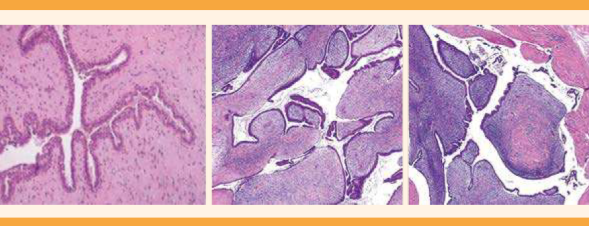

Figura 2 Estudio histopatológico. Puede observarse un patrón bifásico (componente fibroepitelial) con estroma hipercelular, característica que ayuda a diferenciarlo de los fibroadenomas.

Durante la toma de la biopsia excisional (Figura 3) se efectuó el estudio transoperatorio y se reportó un tumor filodes de bajo grado, con sobrecrecimiento estromal ++, hipercelularidad +, mitosis +. El reporte histopatológico fue de márgenes libres de 0.9 centímetros, motivo por el que se optó por un segundo tiempo quirúrgico para ampliación de márgenes en ambas mamas. El tejido mamario resecado se reportó sin lesión.

Figura 3 Biopsia excisional en ambas mamas. El estudio transoperatorio se efectuó durante la intervención quirúrgica, con reporte de tumor filodes de bajo grado.